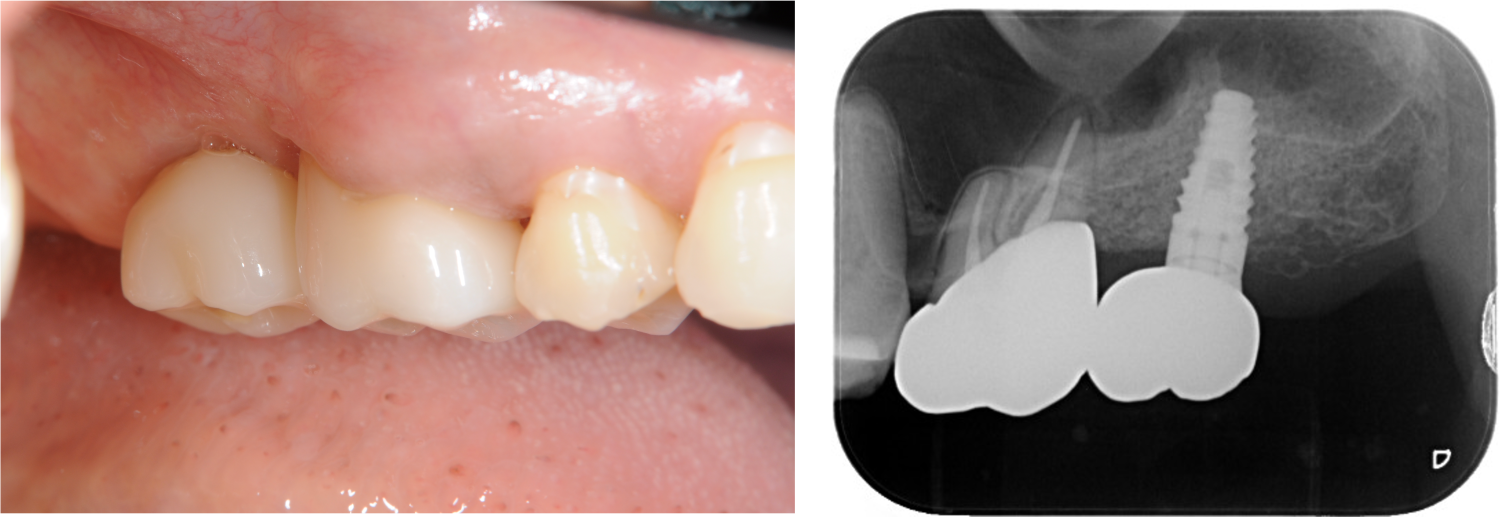

下顎臼歯部が欠損した患者さんのインプラント治療の症例②(うえだ歯科)

| 主訴 | 全顎治療希望、下の奥の歯が無いので全く噛めない。綺麗で噛めるようになりたい |

| 治療内容 | 下顎臼歯部欠損放置のため、臼歯部においてスペースがないため、全顎治療を行い咬合再構成を行う。 早期においてインプラント治療、咬合関係を模索した後、全顎にわたりセラミックによる補綴治療、その後メインテナンスに移行 |

| 治療費 | 5,410,000円(税込)(インプラントすべて含む) |

| 治療期間 | 1年8ヶ月 |

| 治療回数 | 80回 |

| 想定されたリスク | 食いしばり(パラファンクション)によるセラミックの破折、歯の破折 |